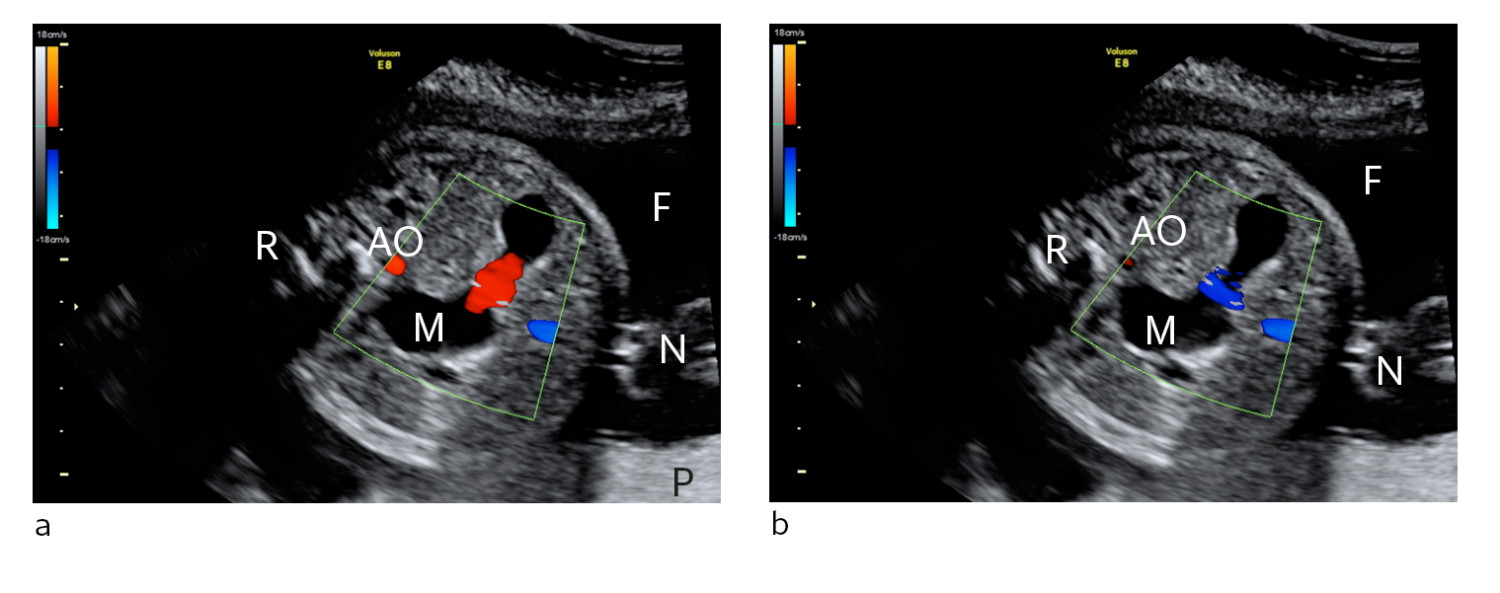

Ny ultralydundersøkelse kl 1115 viste at fosteret hadde normal hjerteaksjon, men det lå helt stille. Blodstrømsmålingene i navlesnorarterien og midtre hjernearterie ble tolket som normale. Klinisk var det ikke tegn til morkakeløsning. CTG-registreringen fortsatte og ble oppfattet som normal (fig 2b).

Dopplerundersøkelse av navlearterie benyttes i overvåking av høyrisikosvangerskap og gir først og fremst informasjon om forhold ved morkaken. Undersøkelsen benyttes for eksempel ved langsom fostervekst og kombineres ofte med undersøkelse av andre føtale eller maternelle kar. Dopplerundersøkelse av midtre hjernearterie kan på samme måte gi informasjon om fosterets tilstand. Ved fosteranemi som for eksempel skyldes immuniseringstilstander vil man forvente høye blodstrømshastigheter i hjernen.